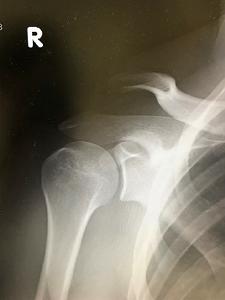

仲が良いのはよいけれど、同じ時期に、しかも同じ右側の肩を・・・

一人は鎖骨骨折、一人は肩鎖関節脱臼を起こしました(笑)。

皆さんは、どっちが骨折で、どっちが脱臼か分かりますか?

正解は、向かって左側が鎖骨骨折、右側が肩鎖関節脱臼でした💛